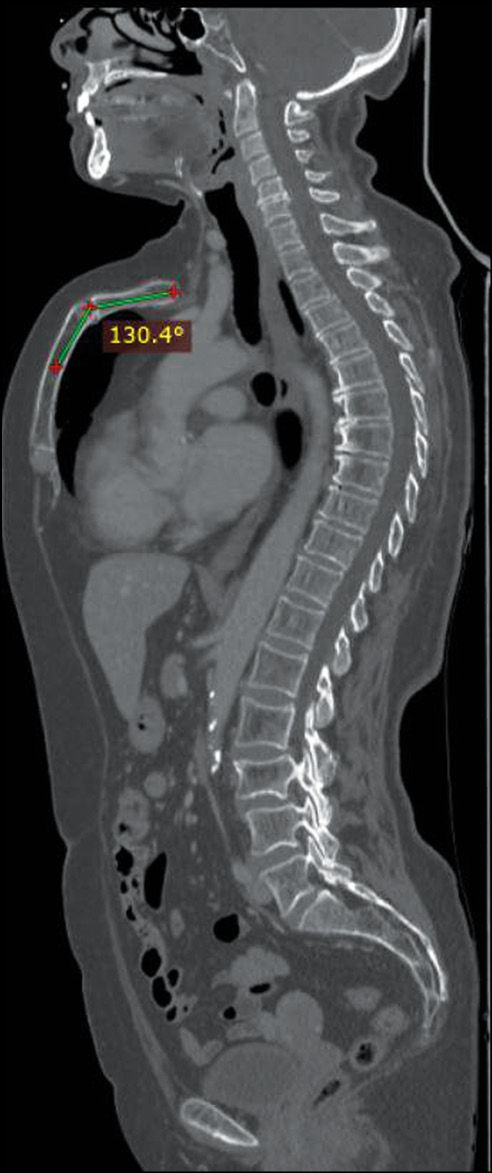

Herein, we present the case of a 66-year-old woman who presented to our clinic for follow-up computed tomography after surgery and chemotherapy for breast cancer with frequent episodes of dyspnea, wheezing, bronchitis, and mild dyspnea annually, which was more frequent during childhood. Computed tomography showed the absence of metastatic lesions and other accompanying diseases, except for a rare deformity of the anterior chest wall, the so-called, a “superior” pectus carinatum, a chondromanubrial deformity with a dorsal-open angle of 130º, and a sternum body length of 9 cm, which is not depressed in the lower third.